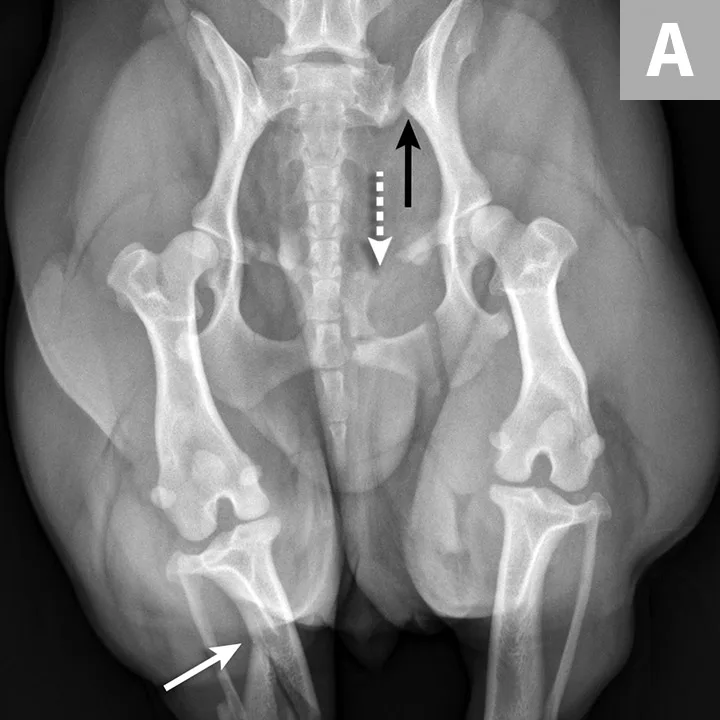

FIGURE 1A

An 11-year-old intact female Welsh corgi with injuries of the weight-bearing axis of the pelvis. Ventrodorsal (A) and lateral (B) projection images show a left sacroiliac luxation with cranial and ventral displacement (black arrow). Pubic fracture with lateral displacement (dashed arrow) and an oblique tibial fracture (white arrows) were additional comorbidities. The tibial fracture was treated surgically with an internal plate fixation, and the pelvic injuries were managed conservatively.